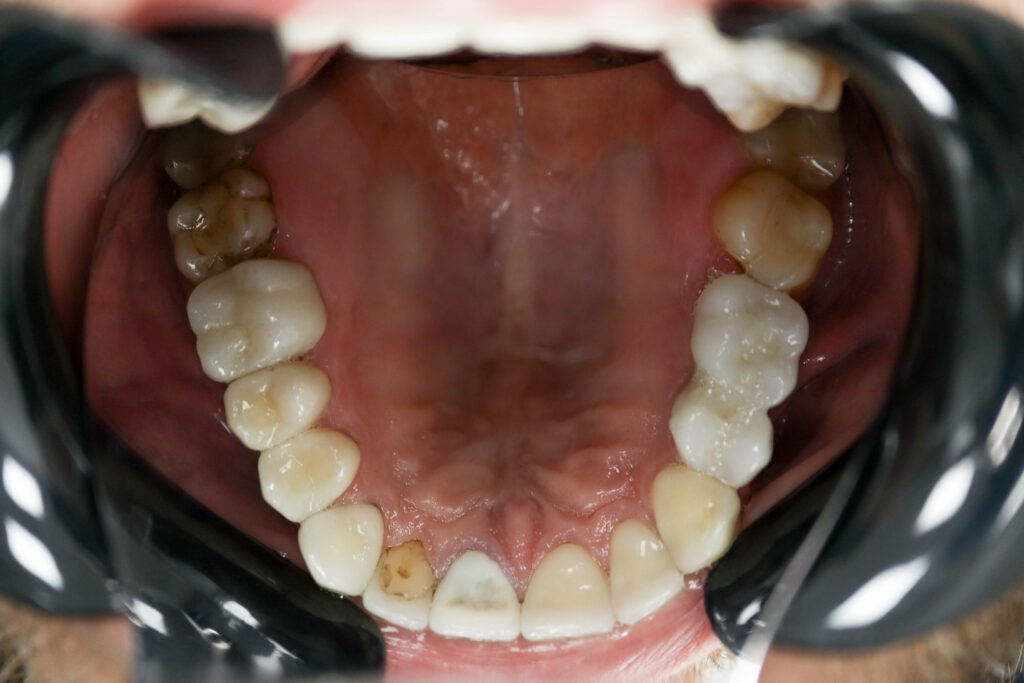

Ситуация до лечения

Пациент обратился с жалобами на эстетические недостатки.

Диагноз: Частичная адентия

Ситуация до лечения Бутримович